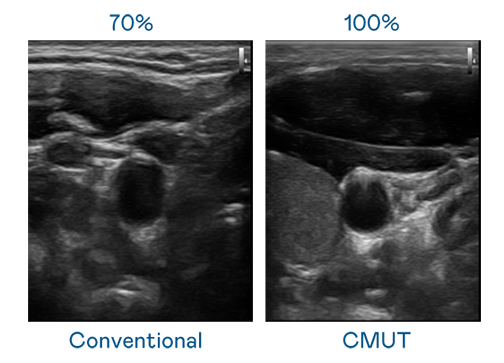

CMUT 技術是一種用電容式微機電元件來產生超音波訊號的技術。與傳統 PZT 壓電式技術相比,CMUT 頻寬增加 30%,更寬頻的超音波訊號讓影像解析度大幅提升,是實現高影像品質醫療超音波掃描、促進精準醫療發展的關鍵技術。

超音波影像的解析度高低,首先取決於探頭能發出的訊號頻寬。PA CMUT 可提供高清晰的超音波訊號,提供高頻寬、高靈敏度、影像紋理細節更高的超音波影像,協助醫護人員縮短影像判讀時間及利用精準的醫療影像進行診斷。